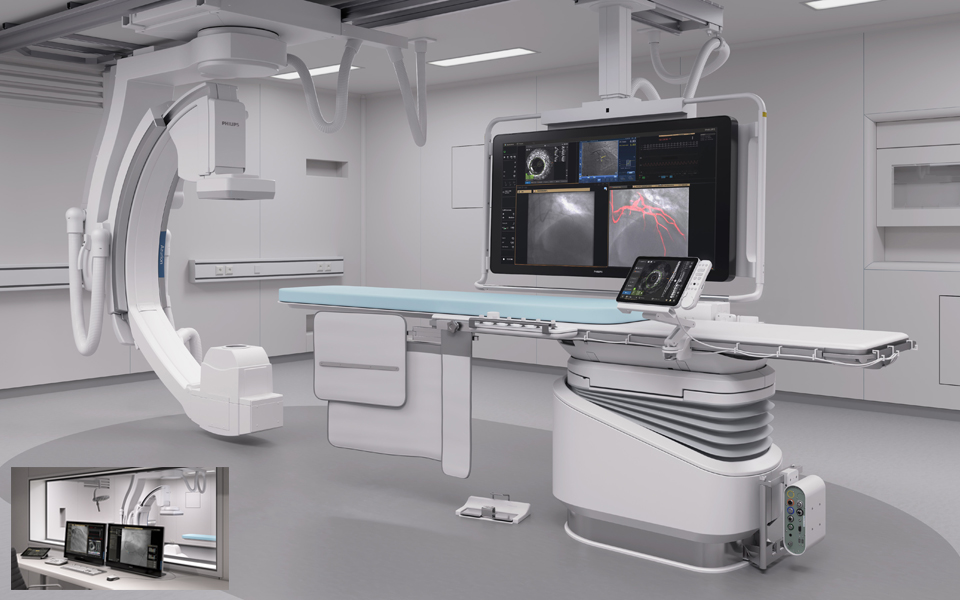

Sistema de terapia guiada por imagen: Azurion

Azurion permite tratar a un paciente más al día, con lo que se reduce el tiempo del procedimiento en un 17%* con opciones optimizadas para el flujo de trabajo en tratamiento intervencionista y software clínico.

Estación de trabajo con aplicaciones intervencionistas: IntraSight

Proporciona información clínica completa con la perfecta integración de iFR/FFR, ultrasonidos intravasculares y herramientas de reposicionamiento automático que mejoran los resultados sanitarios del paciente.You are about to visit a Philips global content page

Visualización clara, orientación fiable: Dynamic Coronary Roadmap

Orientación de navegación automática en tiempo real diseñada para la eficacia del procedimiento en intervenciones complejas de ICP sin afectar al flujo de trabajo estándar actual.You are about to visit a Philips global content page

Módulo de pantalla táctil TSM pro

Módulo de control de pantalla táctil en mesa intuitivo. Controle de forma continua las aplicaciones compatibles en mesa en el campo estéril con el módulo de pantalla táctil Pro mejorado. Acceda a la fisiología, ultrasonidos intravasculares, mediciones hemodinámicas, herramientas intervencionistas y todos los parámetros de adquisición de imágenes para trabajar de manera rápida y decisiva. Controlar estas aplicaciones en la sala de examen puede ahorrar tiempo, reducir el desorden de los equipos y le ayudan a centrarse en el paciente.You are about to visit a Philips global content page

Sistema Interventional Hemodynamic con IntelliVue X3

Aporta mediciones hemodinámicas avanzadas al laboratorio de cateterismo. Se integra con el monitor de paciente Philips IntelliVue X3 para la monitorización continua del paciente antes, durante y después de la intervención.You are about to visit a Philips global content page